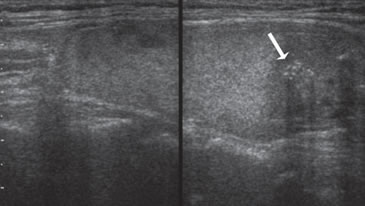

6. Vascularización

Según la distribución de los vasos sanguíneos, los nódulos tiroideos se describen como hipovasculares (Figura 11), isovasculares (los menos frecuentes) e hipervasculares. En los hipervascularizados, se describen dos patrones. Un patrón de vascularización periférica (Figura 12) tiende a ser una característica de lesiones benignas (80-95% de nódulos hiperplásticos y adenomatosos) y un patrón de vascularización central o interna (Figura 13a), con o sin un componente periférico (Figura 13b) se observa en 70%- 90% de los nódulos malignos, aunque hay una considerable sobreposición, por lo que el optimismo inicial de que el “Doppler color” podía diferenciar nódulos benignos de malignos (Figura 13c) se ha ido esfumando gradualmente a medida que han ido apareciendo estudios con mayor número de pacientes18. Es necesario precisar que la mayoría de los nódulos hipervasculares son benignos, debido a que los nódulos hiperplásticos son mucho más frecuentes que los nódulos malignos (Figura 13d). El flujo vascular exclusivamente periférico en un nódulo bien delimitado, es frecuente de observar en nódulos hiperplásticos, y se le ha denominado el signo del “anillo de fuego” al “Doppler color”. Cerca de un 20% de los carcinomas papilares pueden ser hipovasculares (Figura 14a). Un nódulo avascular raramente corresponde a un tumor maligno (Figura 14b).

Figura 13. a) Cáncer papilar sólido,

con vascularización central (flecha) con

vasos intranodulares desorganizados;

b) Cáncer papilar sólido delimitado por

vasos periféricos y un vaso central penetrante

de mayor tamaño (flecha); c)

Nódulo coloideo con un patrón de flujo

mixto, periférico y vasos centrales desorganizados

(flechas) que simulan un

patrón maligno; d) Hiperplasia folicular

que muestra un nódulo bien delimitado

con vascularización aumentada,

central y periférica